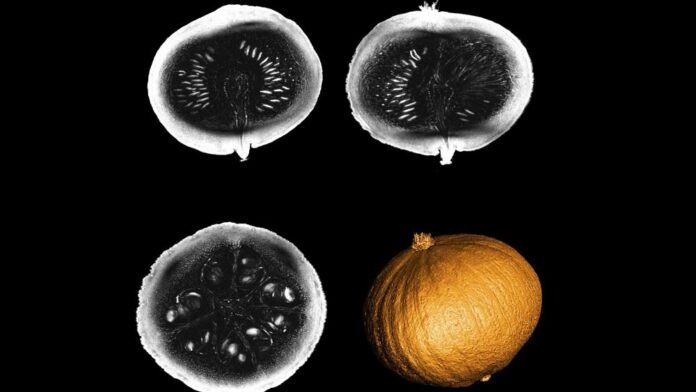

The globe’s most effective MRI scanner, which might have extensive effects in identifying neurological illness, has actually provided its very first photos – of a pumpkin.

Why photos of a pumpkin as well as not a human mind?

” It [the pumpkin] has the exact same size as the mind, an intriguing, complicated interior framework, with grains as well as coarse components – and afterwards it’s the appropriate period,” Lerman stated.

The device goes for a photo resolution of under half a millimetre, a jump onward in the clinical area that will certainly permit “to go far more carefully in the resolution of the spatial frameworks” of the mind.